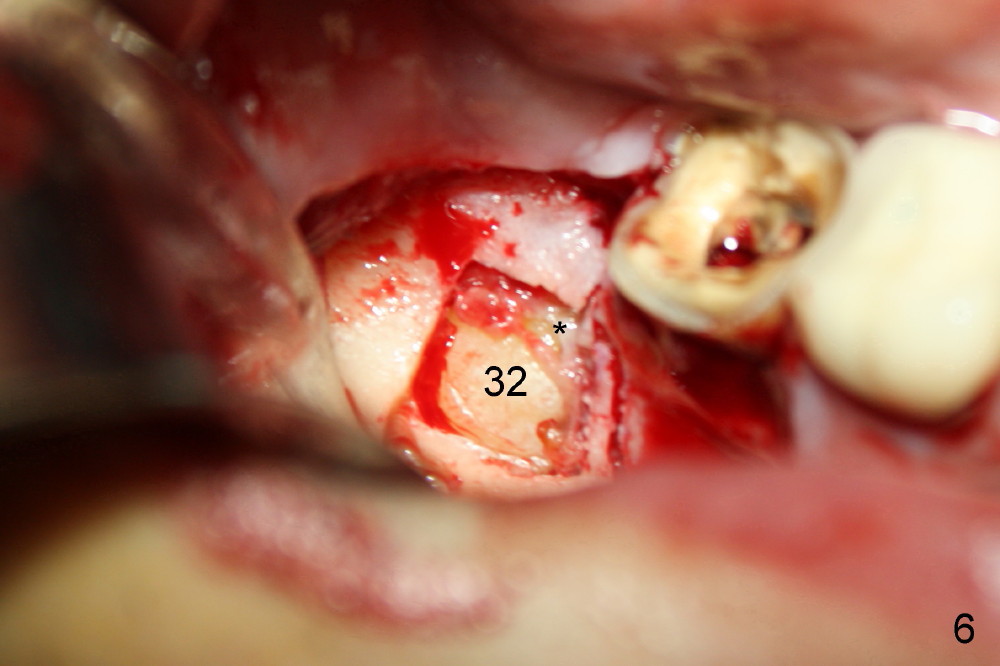

(Fig.4<). A bony window is made (Fig.5*) to expose the impacted tooth of

#32 (Fig.6). The latter is sectioned for easy removal (Fig.7 arrowhead);

there is yellowish exudate from the cyst (*). Nonsalvageability of #31 is

confirmed (Fig.8). Extraction of #31 shows the septum (Fig.9).